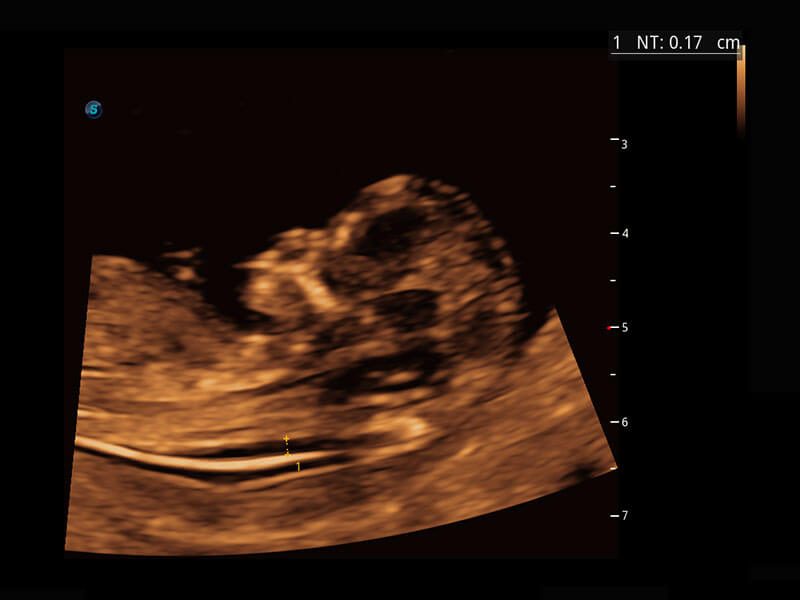

早孕筛查

P60在胎儿早孕期超声筛查中为您带来优异的图像质量。

• 早孕-胎心